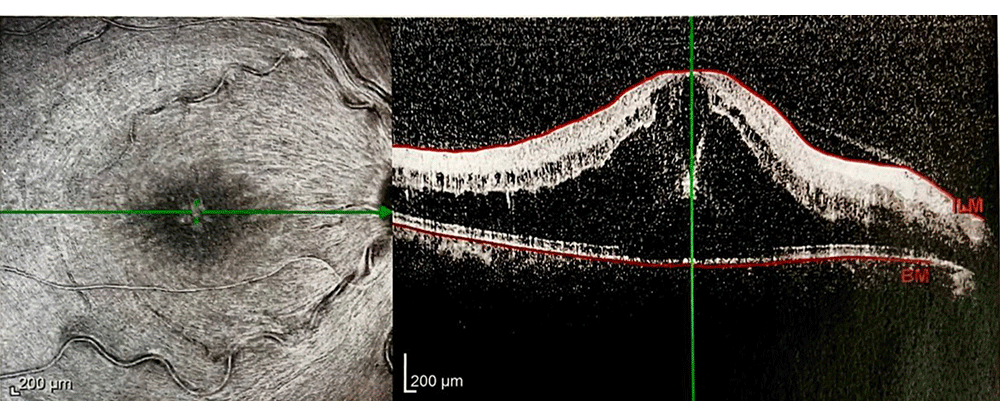

• 2020年9月6日:外院行FFA造影提示右眼视网膜无灌注区以及多处荧光渗漏(资料缺)。行全视网膜激光光凝治疗。

• 2020年11月16日:患者频繁多次复发,再次在本院复查FFA,结果显示仍有多处视网膜无灌注区以及多处荧光渗漏,伴视网膜静脉壁荧光着染及渗漏,考虑有炎症因素存在

• 2020年12月8月:补打视网膜激光,球旁注射TA10mg

• 2020年12月22月:

患者情况】:ME复发时间并没有缩短,基本在25天左右。

治疗】:为延长治疗间隔,和患者详细建议后决定更换抗VEGF药物为:康柏西普(朗沐®)